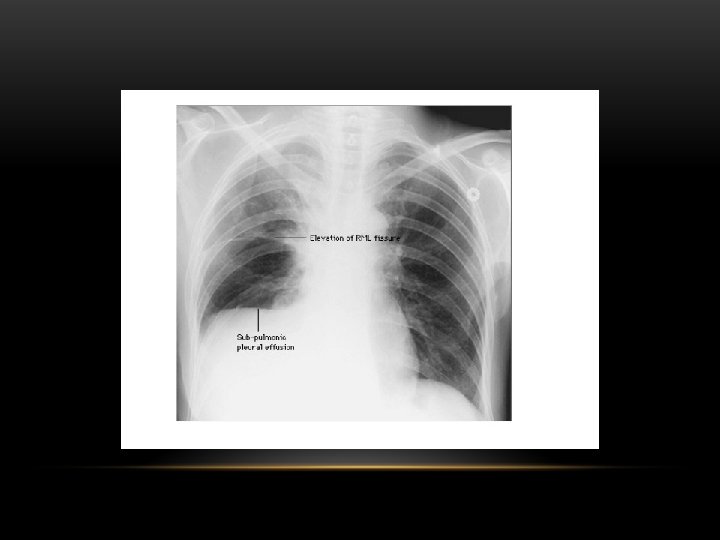

Pleural Effusion Fluid accumulates in the pleural space. Irrespective of the nature of fluid, radiologically they will look similar. Radiological criteria are: Density In dependent portion (Costophrenic angle in PA view). Blunting of costophrenic angle Lack of identifiable diaphragm (silhouette sign principle).

Pleural Effusion • Homogenous density • Loss of cardiophrenic angle • Loss of diaphragmatic and right cardiac silhouette